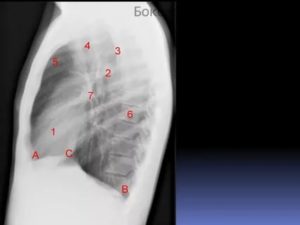

На рентгенограмме подписаны все анатомические структуры, чтобы читателям было легко разобраться. Предлагаем запомнить интенсивность легочных полей. Норма не предполагает наличия патологических затемнений (белого цвета) и просветлений (темного цвета), которых нет на изображении.

Если «набить глаз», научитесь четко отличать норму от патологии.

Рентген здоровых легких описывать следует по классическому стандарту. Вначале вносятся записи о патологических рентгеновских синдромах, затем легочные поля, корни, купола диафрагмы, реберно-диафрагмальные синусы, сердечная тень и мягкие ткани.

Классический алгоритм описания здоровых легких:

- В легочных полях без видимых очаговых и инфильтративных теней;

- Корни не расширены, структурны;

- Контуры диафрагмы и реберно-диафрагмальные синусы без особенностей;

- Сердечная тень обычной конфигурации;

- Мягкие ткани без особенностей.

Вышеприведенная рентгенограмма подпадает под данное описание.